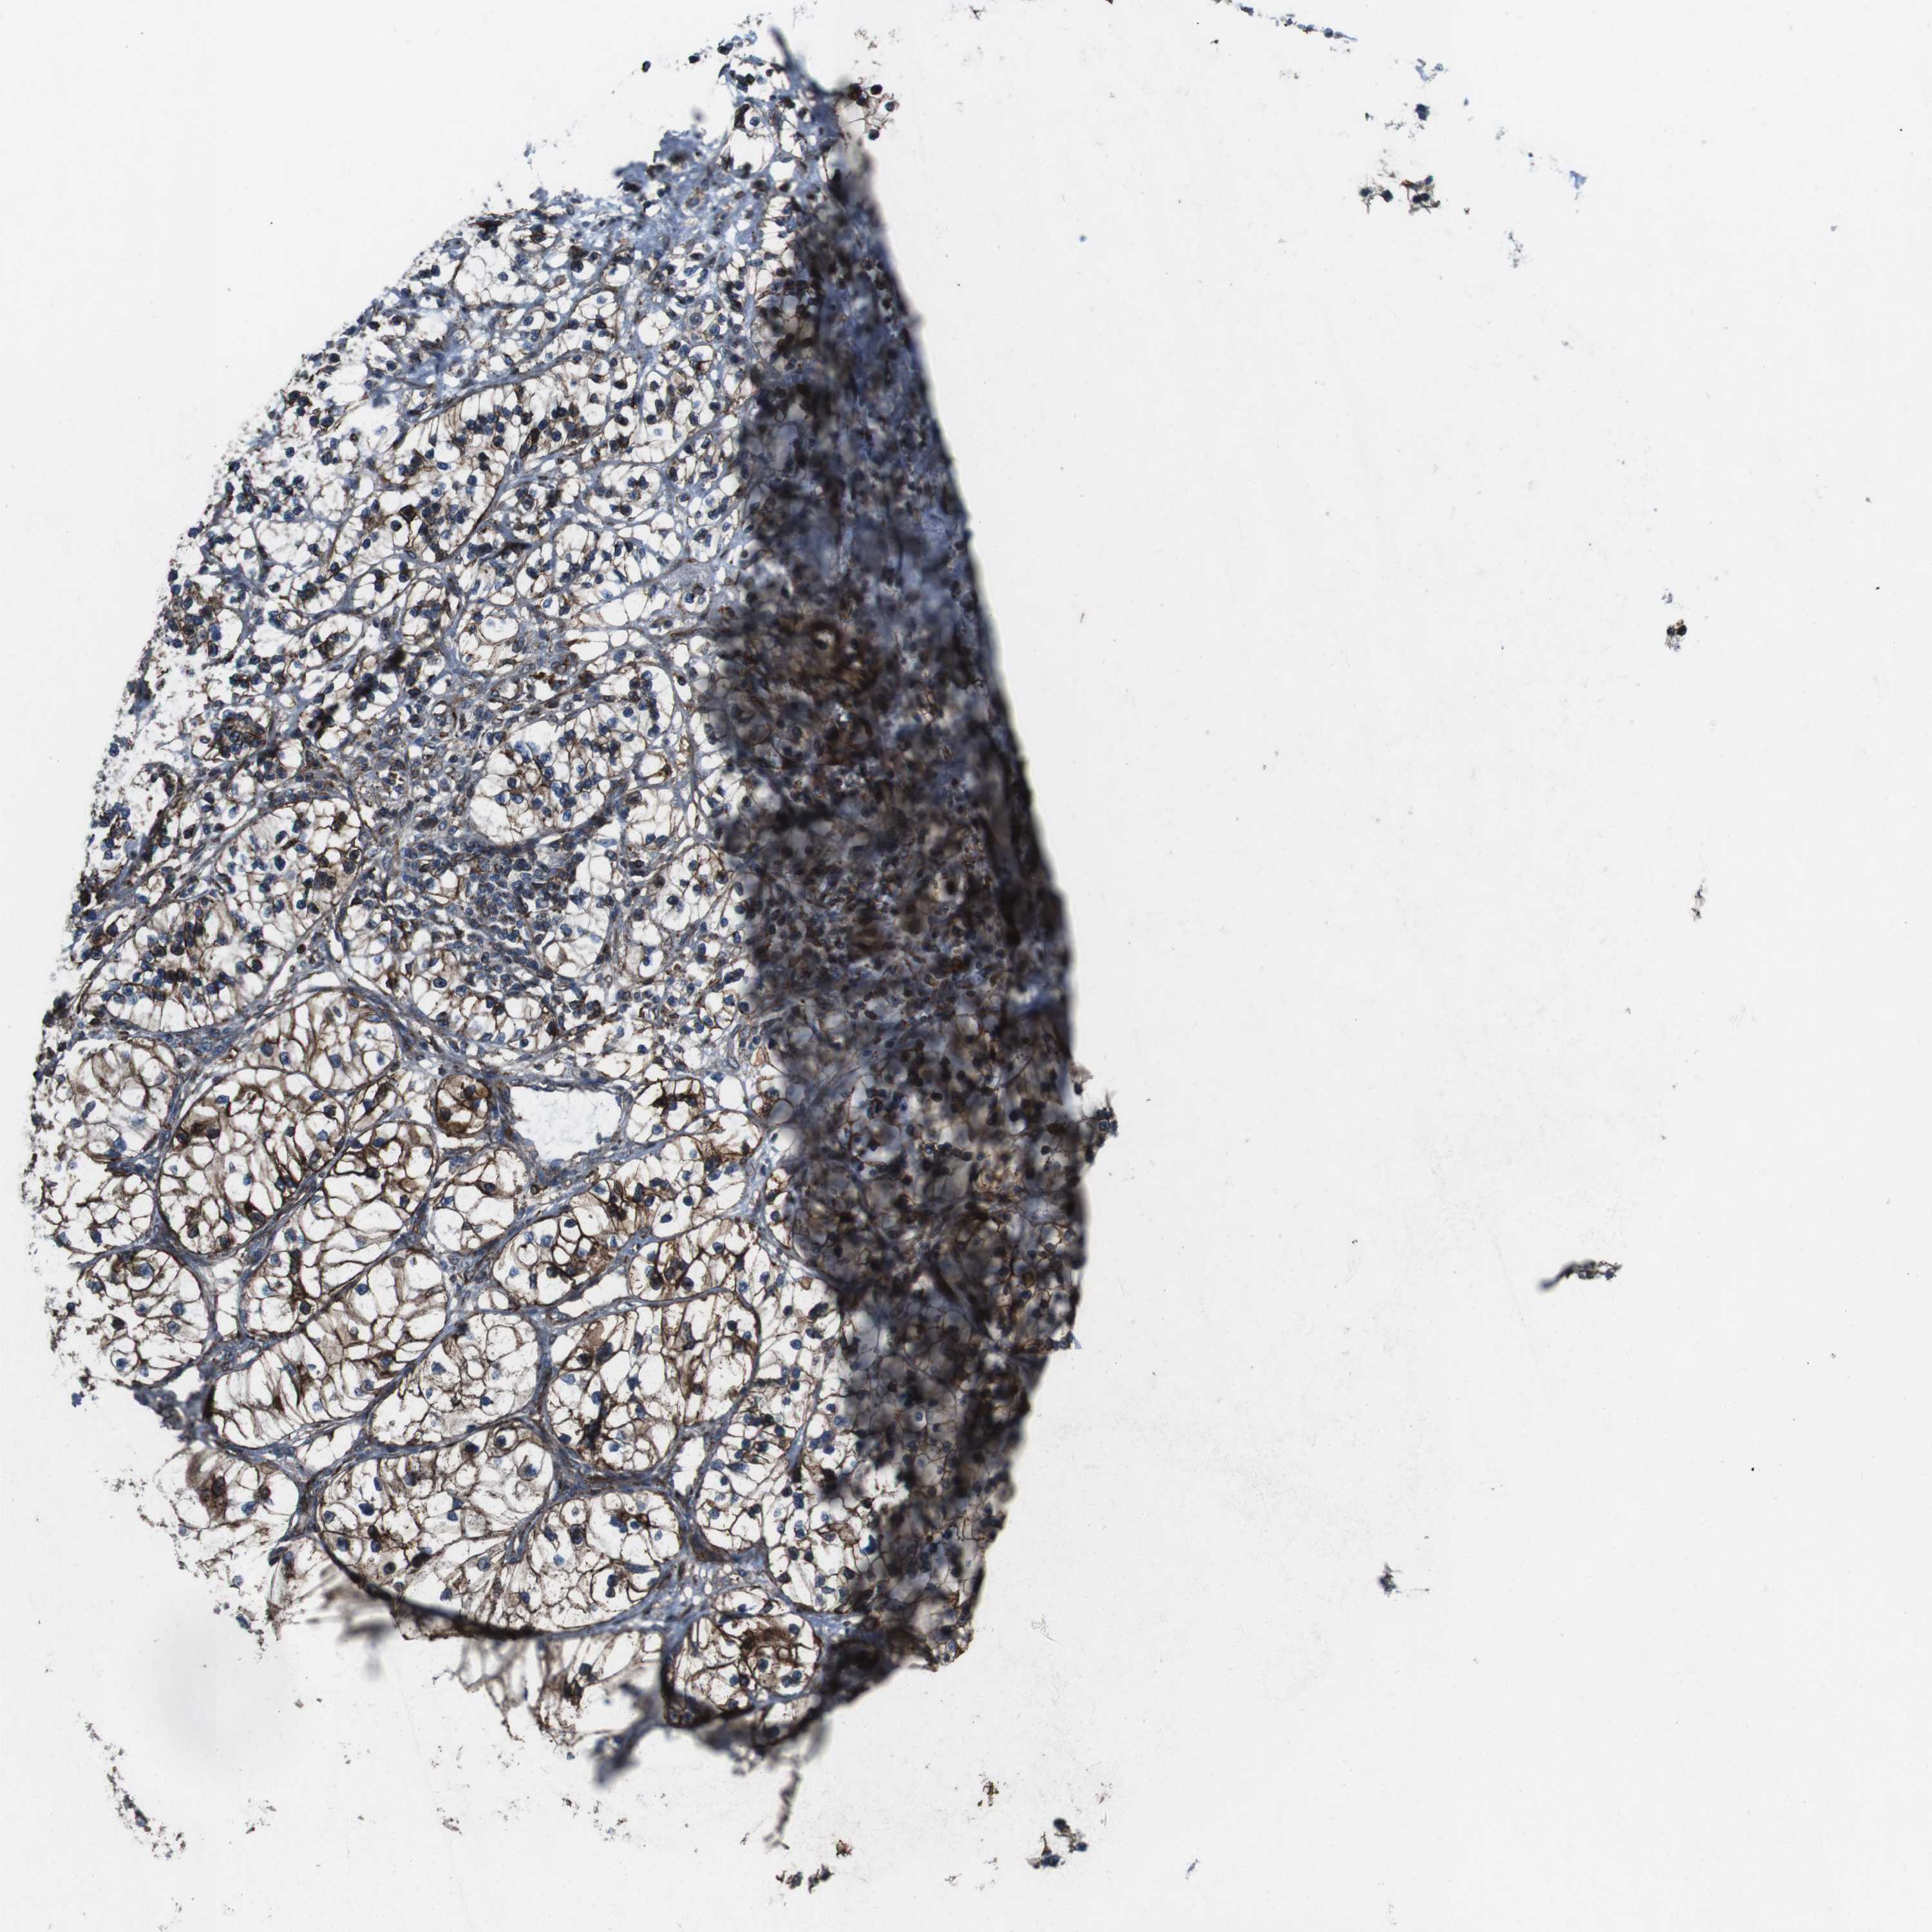

TCGA RNA samplesi

RNA-seq data is reported as average FPKM (number Fragments Per Kilobase of exon per Million reads), generated by the The Cancer Genome Atlas (TCGA) .

Normal distribution across the dataset is visualized with box plots, shown as median and 25th and 75th percentiles. Points are displayed as outliers if they are above or below 1.5 times the interquartile range. FPKM values of the individual samples are presented next to the box plot.

Average pTPM 0.1

Number of samples 100